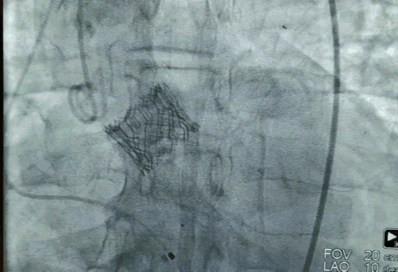

SAPIEN 3瓣膜是一款目前国际上受到广泛认可的介入瓣膜,这也是来永强教授团队第一次应用SAPIEN 3瓣膜行TAVR手术。

SAPIEN 3瓣膜是球扩瓣,后期三度传导阻滞的发生率比较低,起搏器植入率就会低很多,另一方面SAPIEN 3瓣膜相对比较短,对如第二例冠脉开口比较低的患者,相对来说风险低一些。

“三例手术,没有一例出现传导问题,结果让人惊喜。”

周玉杰教授在术后表示,SAPIEN 3瓣膜相比自膨瓣定位更好,瓣膜的缝合程度和瓣环的镶嵌程度适合,瓣周漏少。而且起搏器植入率、并发症发生率都较低,整个操作系统简化,从输送系统的先进性、瓣膜的先进性、瓣膜的血管对主干的影响、位置上下滑动的一些控制等,SAPIEN 3瓣膜都是一个良好的瓣膜。

“但无论是球扩瓣还是自膨瓣,医生需要做的就是选择最适合患者的。”周玉杰教授强调。